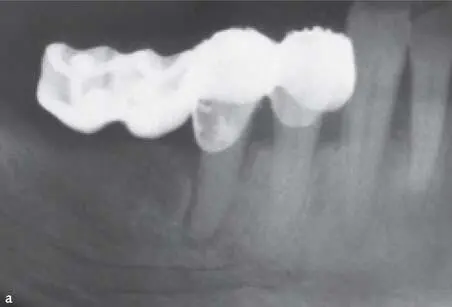

Fig 1-2-12 Partially edentulous patient with a combination of primary and secondary deep bite due to loss of molar support and significant tooth wear.